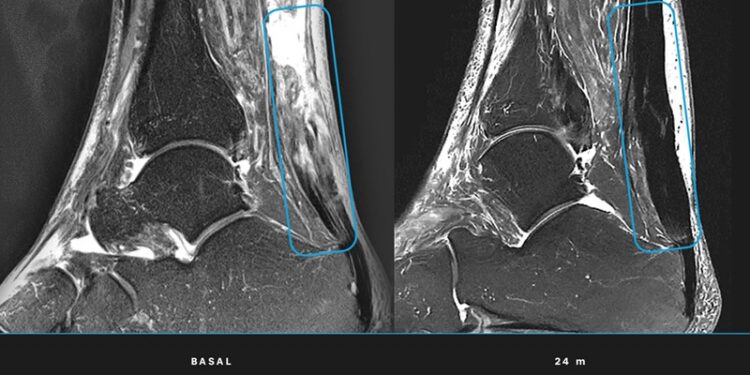

- Regeneración total: Las resonancias magnéticas confirmaron que todos los pacientes alcanzaron la regeneración completa del tendón al término del seguimiento de 24 meses.